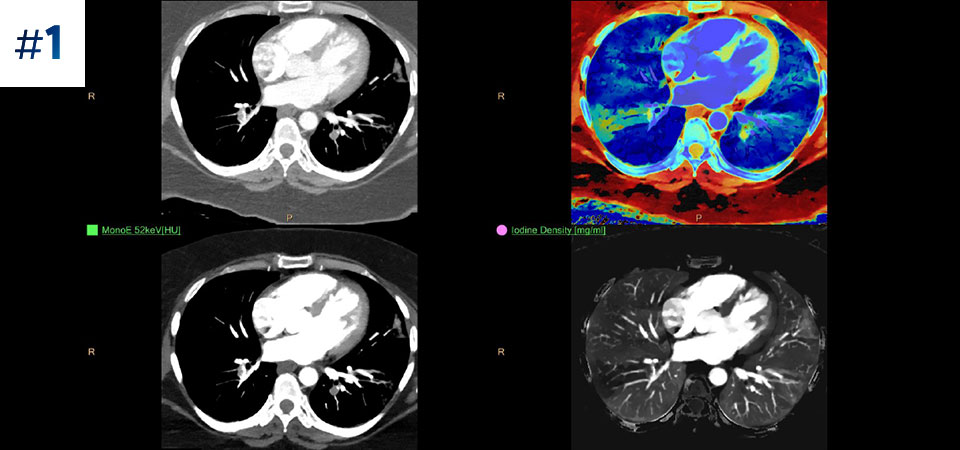

Go beyond conventional CT. See how layers of spectral-detector results can enhance your diagnostic confidence.

See the difference between spectral-detector CT and conventional CT

Reduced follow-up exams Improved tissue characterization and visualization may reduce the need for follow-up scanning for sub-optimal exams and incidental findings.